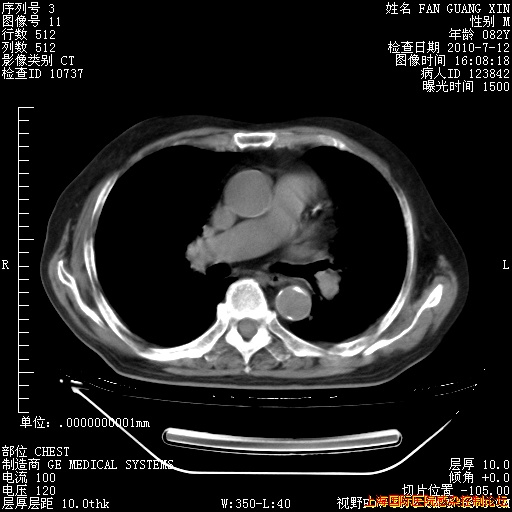

6月12日纵膈窗

整整相隔30天的肺部CT好像有所好转啊。甲强龙减量第3天,需要观察体温。

海管,自昨日你和我通完话后,不知您岳父消化道症状有无缓解?体温怎样?阅读7.12日胸部ct,个人认为目前激素治疗是有效的,甲强龙减量是适宜的。因在抗痨治疗,需密切观察肝功、肾功能和血常规。不过,老年、长期住院和大量使用激素,很担心菌群失调发生